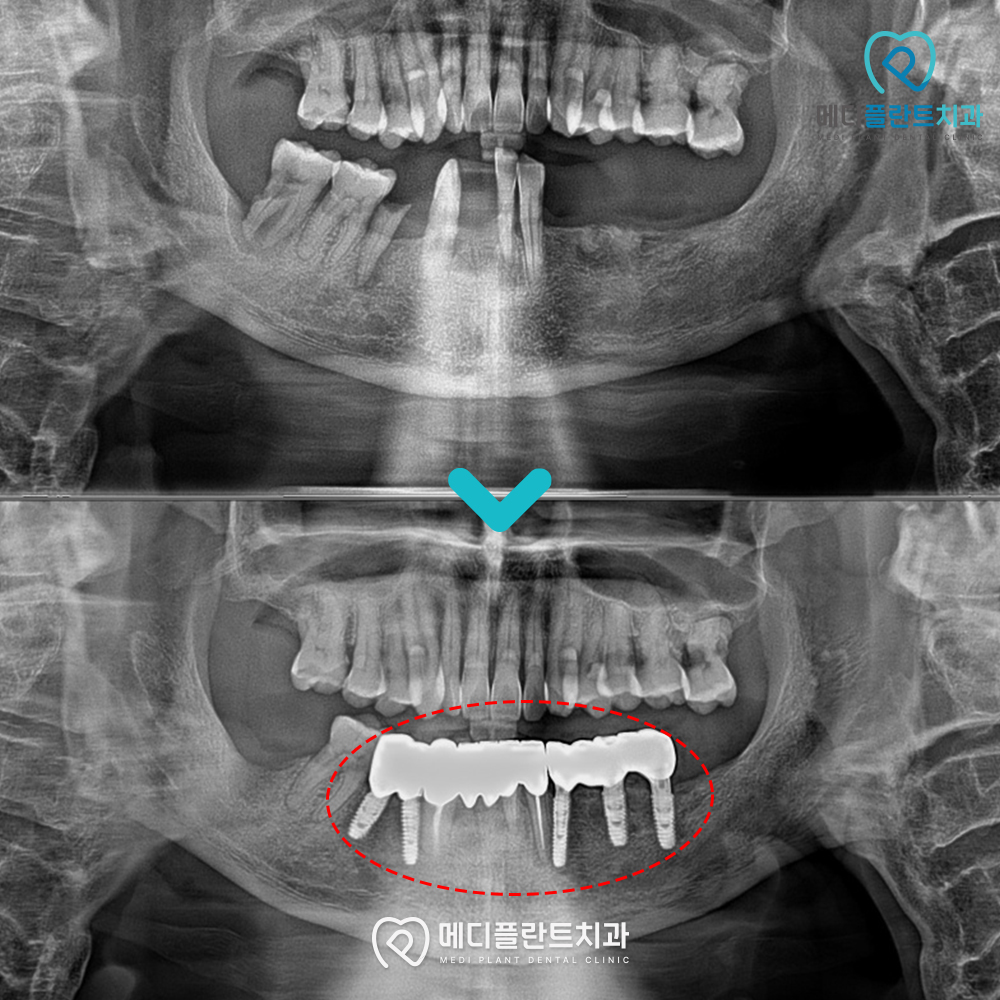

치료 전 촬영한 파노라마 사진을 확인해보면

하악 치아가 전반적으로 많이 상실된 상태였고,

남아 있는 치아 역시 기울어지거나

지지력이 부족한 상태였습니다.

치료 후 파노라마 사진을 보면

임플란트가 안정적으로

자리 잡은 모습을 확인할 수 있는데요.